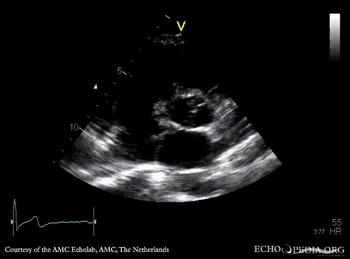

A4CH: Eustachian valve in right atrium